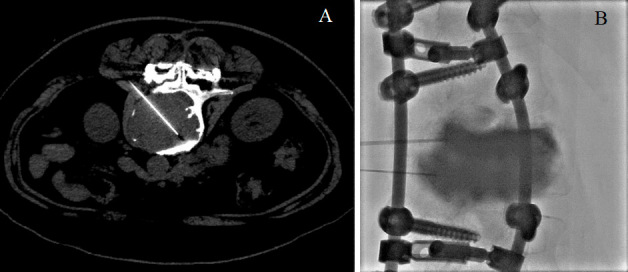

Abstract Image